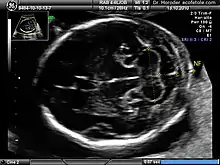

Down syndrome

Enlarged NT and absent nasal bone in a fetus at 11 weeks with Down syndrome